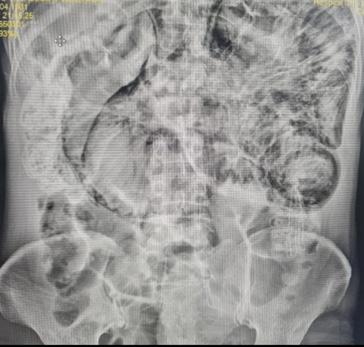

Pneumatosis intestinal por Enteritis lúpica, manifestación poco frecuente de lupus eritematoso sistémico

Intestinal pneumatosis due to lupus enteritis, a rare manifestation of systemic lupus erythematosus

Alejandra Vargas, Juan Candia................................................................................................................81-87